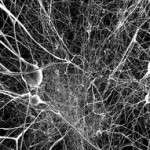

Nuovi neuroni sono generati abbondantemente in molte regioni del cervello molto giovane. In un cervello maturo, la formazione dei neuroni rallenta notevolmente, ma si estende in seguito generalmente nel giro dentato, costituito dall’ippocampo propriamente detto, dalla corteccia entorinale e dal subicolo e bulbo olfattivo che è la prima stazione di elaborazione delle informazioni trasportate dai neuroni olfattivi. Loepke e dei suoi colleghi di ricerca, collaborando anche con i ricercatori dell’ University of Cincinnati College of Medicine e l’Ospedale dei Bambini di Fudan University, Shanghai in Cina, hanno prestato particolare attenzione, nel loro studio, al giro dentato, che aiuta l’apprendimento e il controllo della memoria.

Secondo i ricercatori neonati e giovani topi adulti esposti a un anestetico largamente utilizzato chiamati isoflurano, in dosi simili a quelle utilizzate nella pratica chirurgica, hanno perdita neuronale diffusa nelle strutture del prosencefalo, come confermato da precedenti ricerche, senza alcun impatto significativo sul giro dentato. Tuttavia, l’effetto su giovani topi si è invertito, con il minimo impatto neuronale nelle regioni proencefalo e morte cellulare significativa nel giro dentato.

Il team ha poi effettuato studi approfonditi per scoprire che l’età e la maturazione dei neuroni colpiti erano le caratteristiche che determinano la vulnerabilità alla morte delle cellule neuronali indotta da anestesia. I ricercatori hanno osservato risultati simili nei giovani topi adulti.